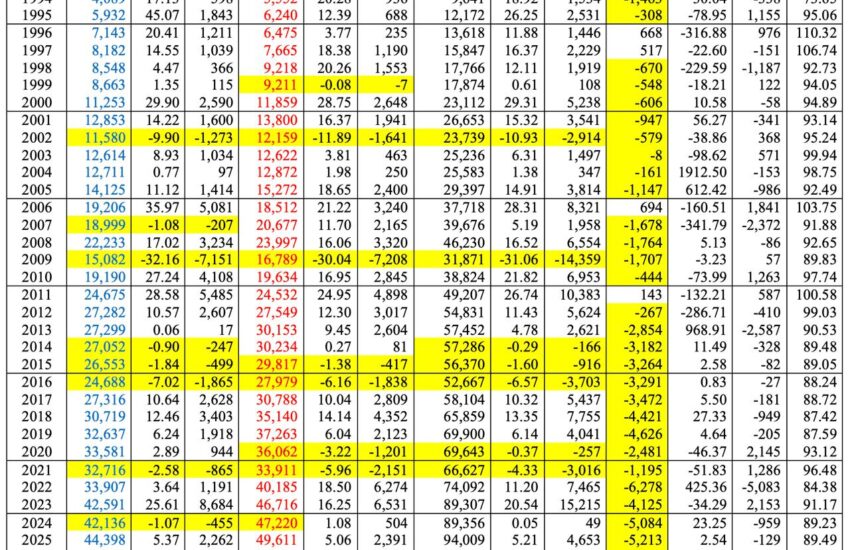

Estudios del Instituto Mexicano del Seguro Social (IMSS) estiman que el costo promedio anual por paciente con EPOC asciende a $89,479 pesos, siendo los medicamentos el principal componente del gasto, con más del 68% del total [3]. En grupos de alto riesgo —como adultos mayores expuestos al humo de tabaco o leña— la prevalencia puede alcanzar hasta el 25%, lo que proyecta un costo nacional superior a $347 mil millones de pesos anuales.

Un estudio publicado en Value in Health revela que el costo por paciente con EPOC varía según la gravedad, desde $1,500 USD en etapas leves hasta $23,717 USD en casos graves con exacerbaciones, siendo estas últimas las que concentran la mayor carga económica para el sistema público de salud. El análisis concluye que el diagnóstico oportuno y el control temprano de la enfermedad pueden reducir significativamente los costos asociados a hospitalizaciones, cuidados intensivos y uso de oxígeno [4].